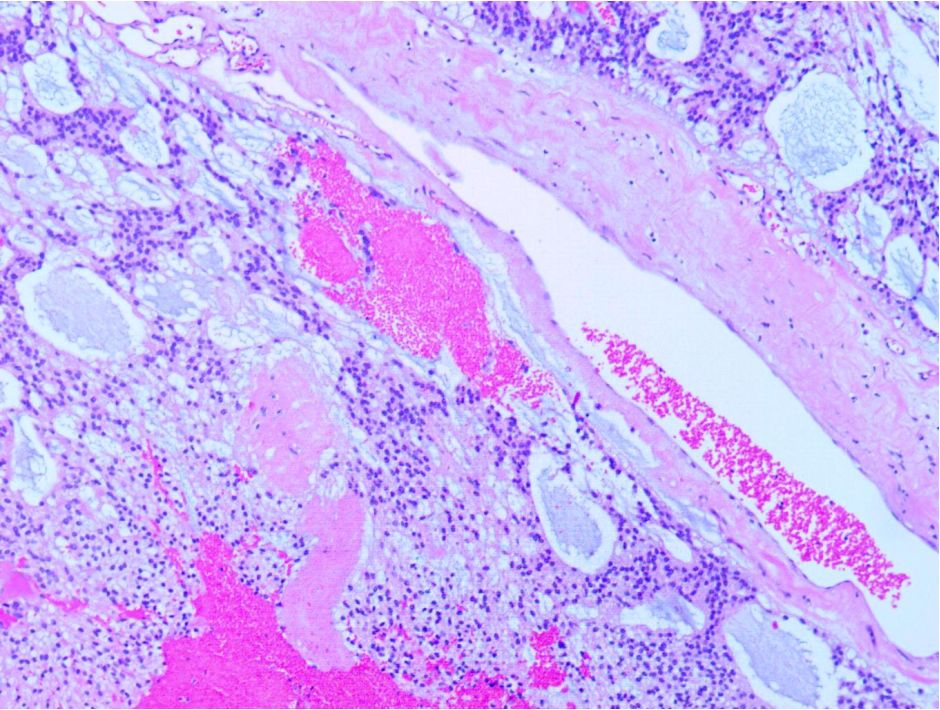

图3. 术后常规病理结果:(胸10-腰1椎管内)粘液乳头状室管膜瘤,WHO I 级。免疫组化结果:EMA -,GFAP +,S-100 -,Vimentin +,CD99 +,CD56 +,P53 -,Ki-67 <2%+,CK(AE1/AE3) -,EGFR -。